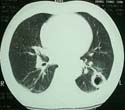

ÈäºÎ Àü»êÈ´ÜÃþÃÔ¿µ

ÇʼöÀûÀÎ °Ë»ç·Î

Æó¾ÏÀÇ ¹ß°ß ¹× º´±â ÆÇÁ¤¿¡ ÇʼöÀû

ÈäºÎ

X¼± »çÁø Àü»êÈ´ÜÃþÃÔ¿µ°Ë»ç